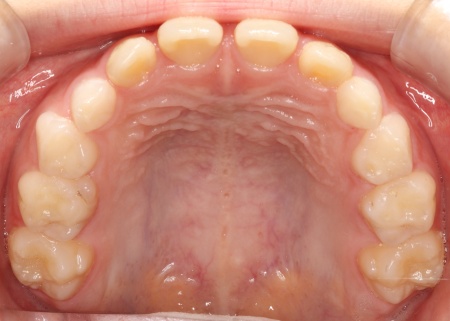

治療後

お子様の成長に合わせて慎重に治療を進めることで、無理のない自然な形で歯並びと噛み合わせを改善することができました。

矯正治療が終了したあとは、治療後の状態を安定させて後戻りを防ぐための「保定装置」を装着し、経過観察を行います。

この段階でも定期的に通院いただいて、良好な状態が維持されていることを確認しました。

現在も保定装置を継続して使用していただいているため、安定した状態を保っています。